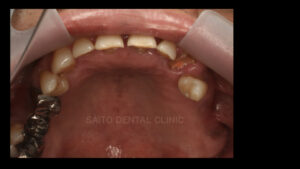

お口の中を見せていただくと左上の奥歯と右下の奥歯が失われています

そして前歯がうまく噛み合っていないので実質噛める歯がほとんどなく

奥歯が壊れるに従って噛み合わせの高さも失われて下の前歯が上の顎に刺さってしまうような状態です

そこでまずは本来の噛み合わせの高さに戻すためにマウスピースを製作しまず上の歯を揃える計画を立てます